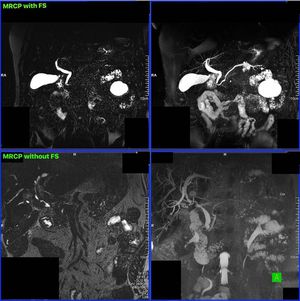

Magnetic resonance cholangiopancreatography (MRCP) is an MRI technique that is used to visualize the biliary and pancreatic ducts in a non-invasive manner. MRCP makes use of heavily T2-weighted MRI pulse sequences (3D T2-w SPACE or/and 2D thick slab HASTE). These sequences show high signal in static or slow moving fluids within the gallbladder, biliary ducts and pancreatic duct, with low signal of surrounding tissue. Regarding its history, MRCP was introduced in 1991. Figure shows 3D T2-w SPACE MRCP with (upper row) and without (bottom row) fat suppression. I personally prefer to use fat suppression on MRCPs. Your thoughts? Images courtesy of Bac Nguyen. #MRI #Siemens_MRI #MRCP #liver #liver_imaging #MRI_Technologist